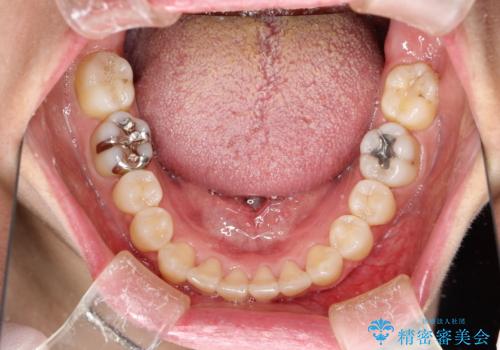

インビザラインによる矯正治療(非抜歯) 前歯の突出と上下の歯並びのガタつきの改善

- 上下の歯並びにガタつきがあり、また、上下前歯の前後のズレが大きく上の前歯が突出しています。

インビザラインではガタつき(叢生)の改善だけでなく、上下の前後的なズレについてもアプローチが可能です。

インビザラインの特色を生かした歯牙移動計画を作成し、非抜歯にて治療を行いました。

マウスピース枚数 初回52枚 + 追加19枚 + 追加12枚

上の歯列に後方への力をかけるために、患者様には顎間ゴムをマウスピースと共に併用してもらいました。